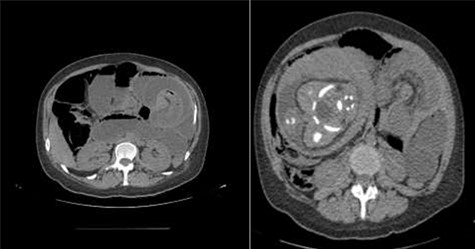

Physical examination presented normal vital signs. The abdomen was tender but lacked signs of peritonitis. Blood analysis revealed leukocytosis, neutrophilia and elevated lactate dehydrogenase. Obstetric ultrasonography (US) showed: fetus at cephalic presentation with good vitality, regular amniotic fluid volume, placenta without detachment. An abdominal computed tomography (CT) scan revealed proximal jejunal dilation caused by an ileoileal invagination and collapsed distal ileum (Figs 1 and 2). Betamethasone and atosiban were administered, and a supraumbilical laparotomy was performed. The intussusception in the common limb (80 cm distal to jejunojejunostomy) (Fig. 3) was reduced (Figs 4 and 5) with progressive and complete intestinal vascular perfusion (Fig. 6). The postoperative period was uneventful, and a caesarian was performed 4 weeks later. At the 45-month follow-up, there was no recurrence.

Coronal view of the CT scan showing intussusception (white arrow—sausage-shaped thickened bowel Wall).